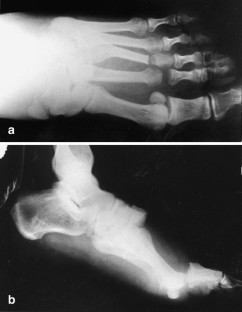

We report an unusual case of concomitant plantar tarsometatarsal (Lisfranc) and 1st and 2nd metatarsophalangeal (MTP) joint dislocations and fracture of the neck of the third metatarsal bone which has never been reported before. The plantar dislocation of the Lisfranc joint was treated by open reduction and fixation with K-wires; the dislocations of the MTP joints and neck fracture of the third metatarsal bone were treated by closed reduction and percutaneous fixation with K-wires and immobilized with a plaster cast. At the 5 year follow-up examination, our patient had no complaints, but the radiograph showed degenerative changes of the Lisfranc and the 1st MTP joint.

Fig. 3a,b.